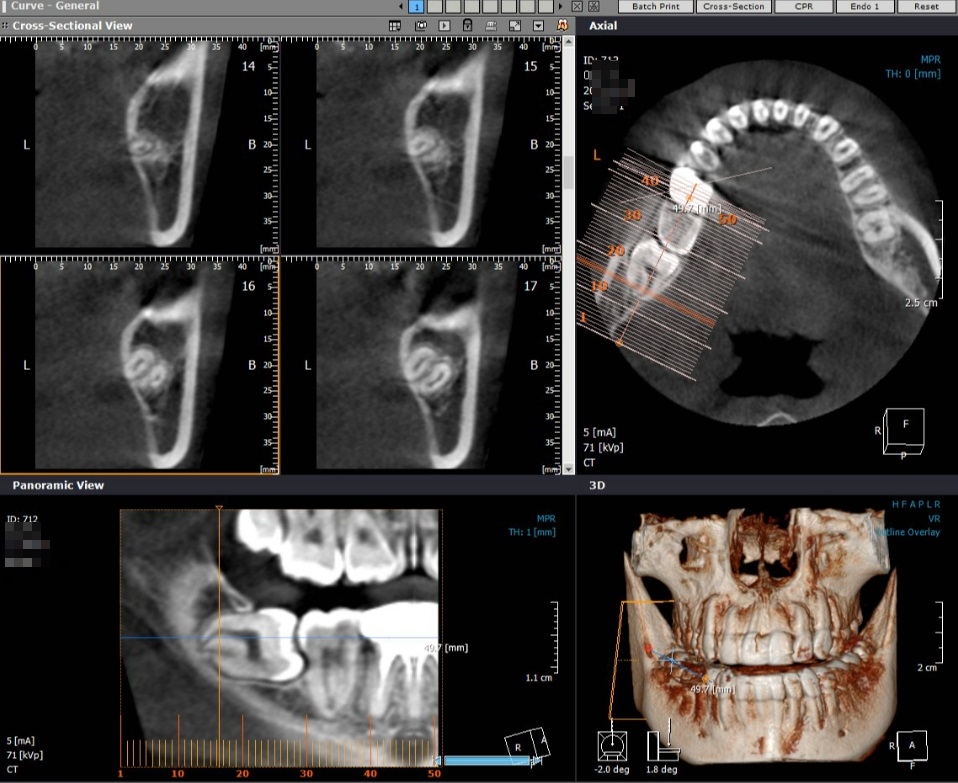

매복치 발치시 파란 선의 신경선의 위치와 치아뿌리의 위치를 확인하기 위해 필요시 CT촬영이 필요하기도 합니다.

사랑니 매복치아 발치의 경우 난이도가 높고, 조심해야할 부분이 매우 많아 CT보유 및 숙련된 치과의사에 의해 발치되어야 합니다.